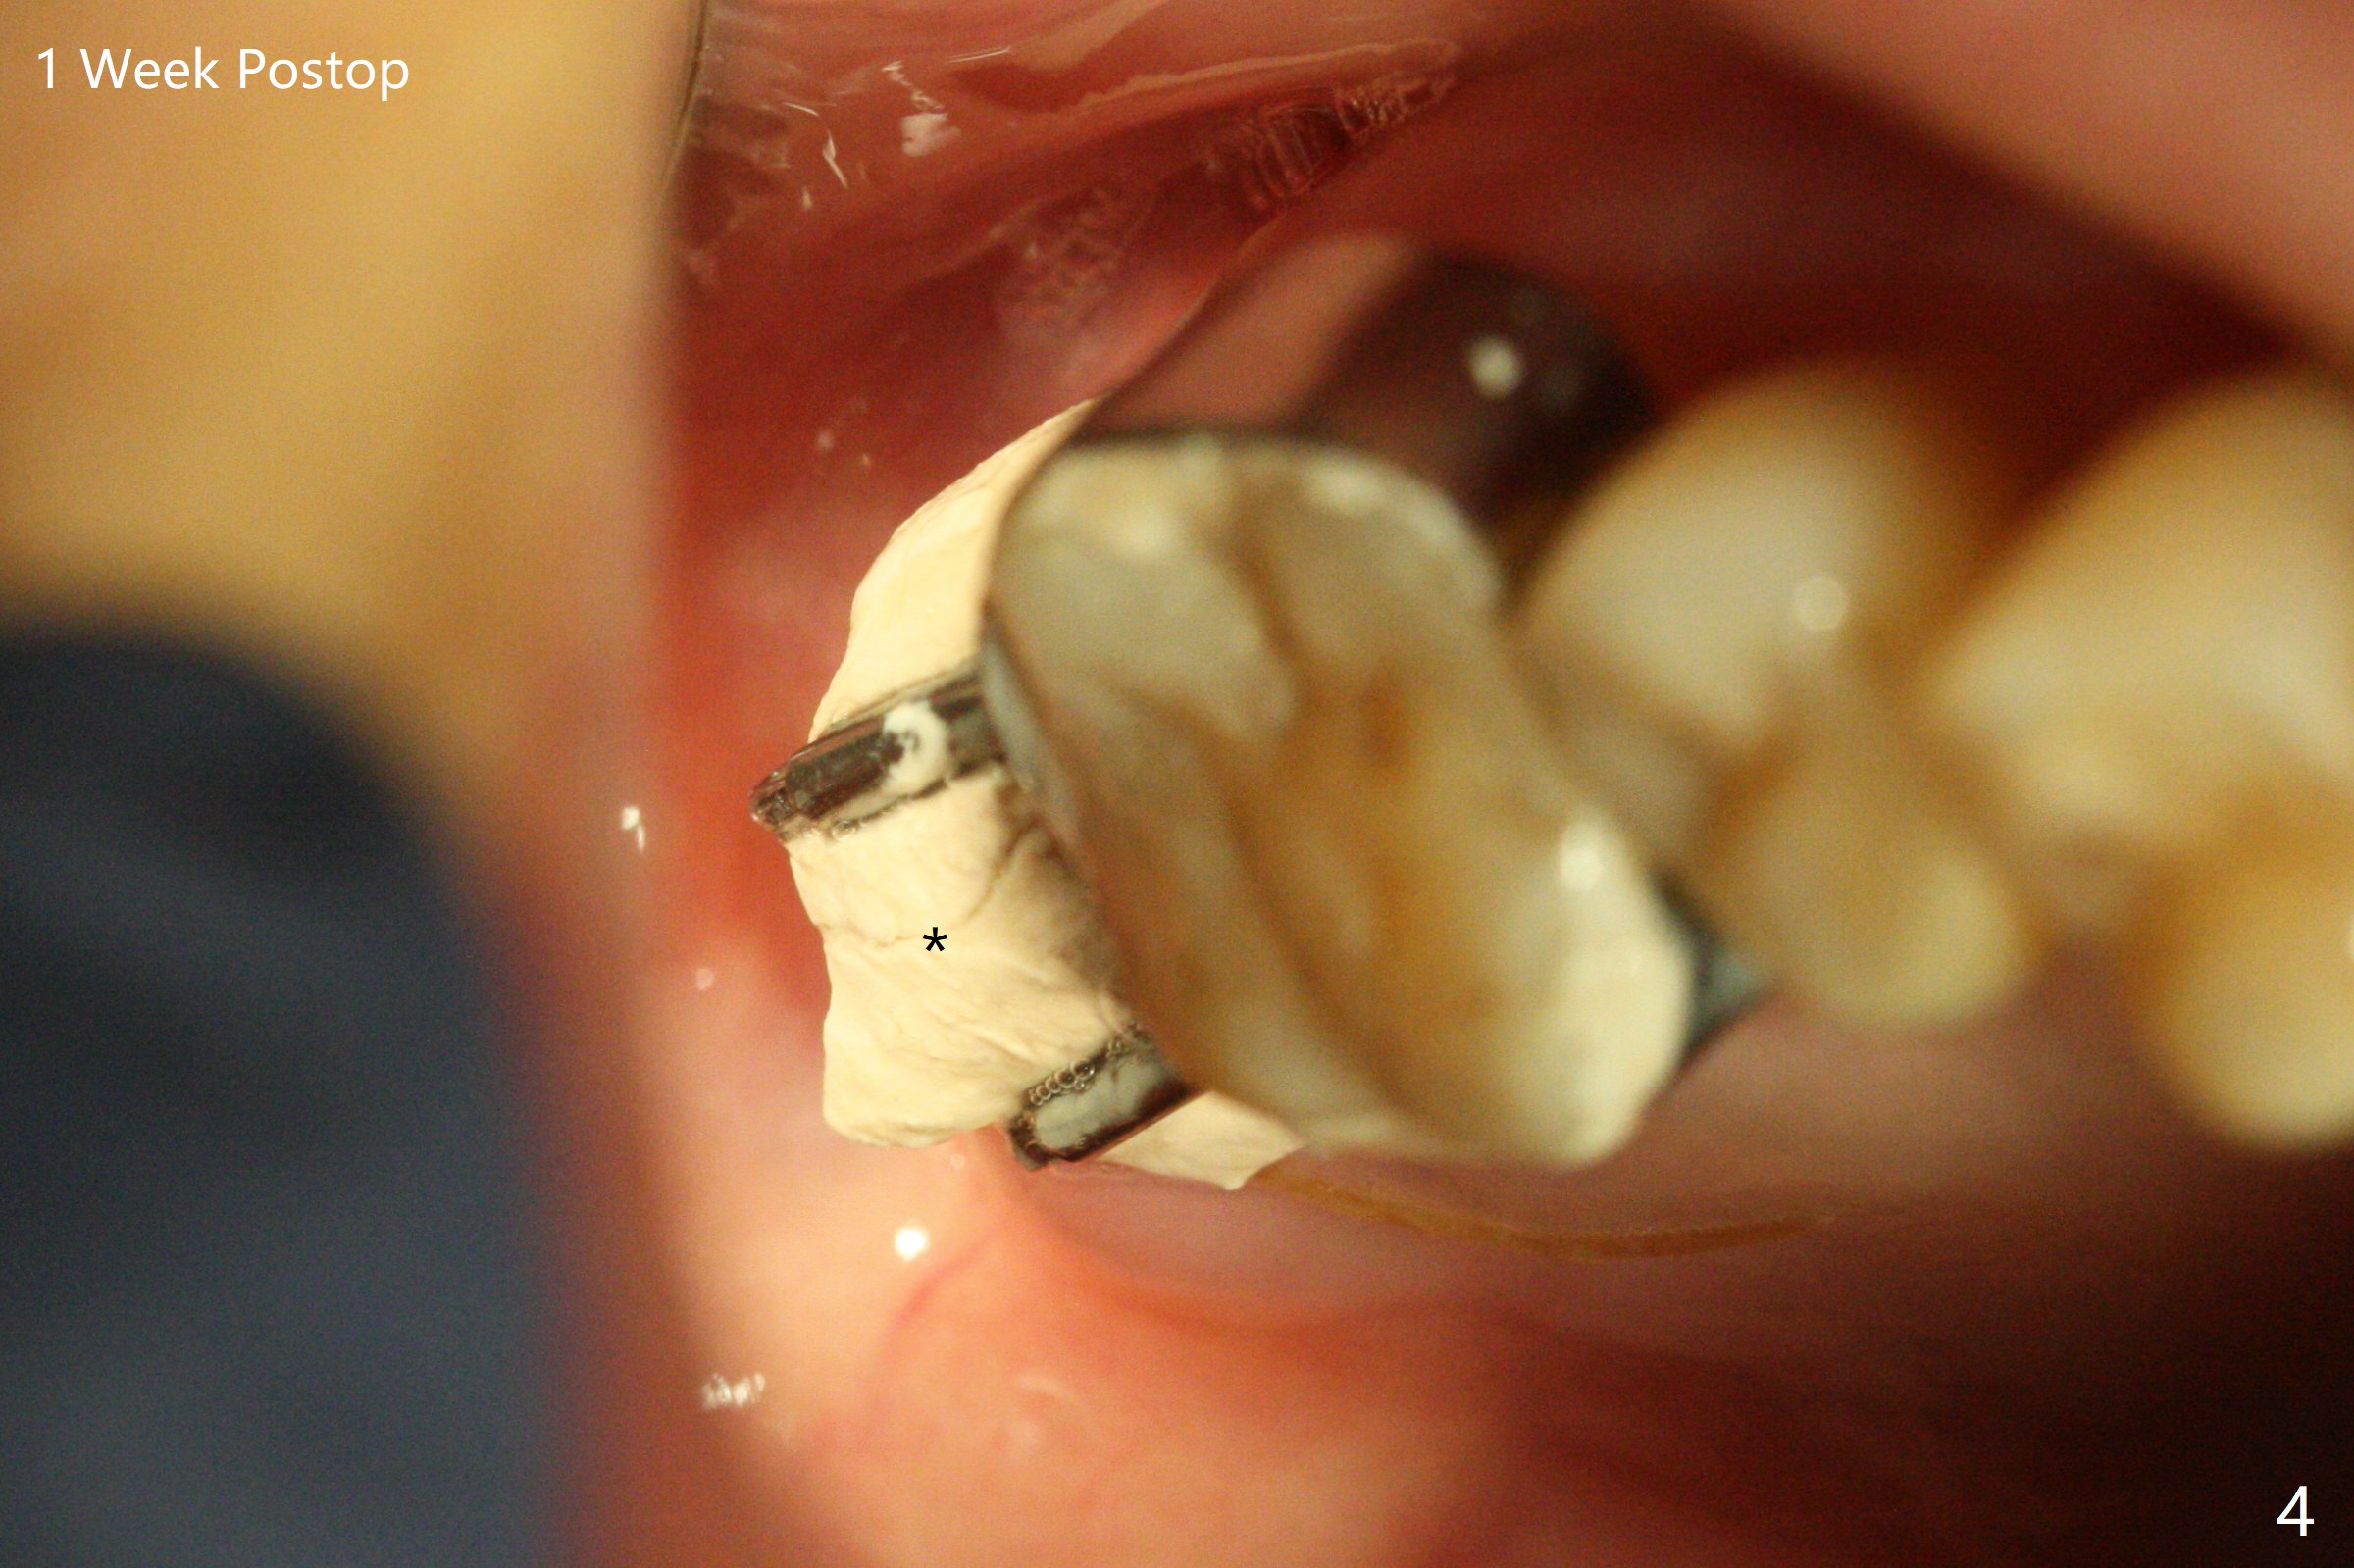

A 55-year-old woman requests extraction of the tooth #2 with pain and mobility a few weeks post SRP (Fig.1) and finally agrees with socket preservation (Fig.2,3 *). In fact the mesiobuccal root appears to have been fractured. She is a heavy bruxer (nuts). There is a large amount of granulation tissue in a large single socket. After suture fixation over Osteogen plug and allograft (*), a prefabricated band (B) and loop (L) are cemented in place. Periodontal dressing is applied mainly underneath the loop for wound protection and bone graft and membrane fixation. The central portion of the periodontal dressing remains in place over the socket opening 1 week postop (Fig.4). The removable distal portion of the loop dislodged 23 days postop. The free end of the fixed mesial portion of the loop is irritating; the patient returns the following day. After removal of the spacer, the socket appears to have healed (Fig.5). No bone graft has been lost (Fig.6 *, as compared to immediately postop (Fig.2,3)). Return to Upper Molar Immediate Implant, Trajectory Xin Wei, DDS, PhD, MS 1st edition 04/13/2019, last revision 01/06/2020